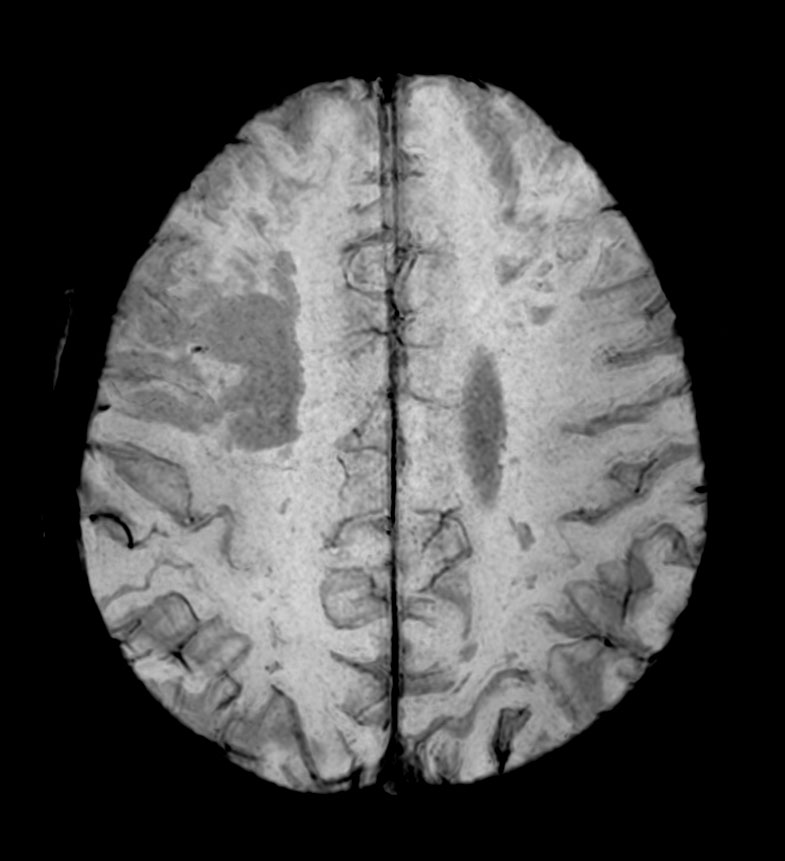

Patient with multiple brain lesions. The ExamCard includes Compressed SENSE to accelerate the entire exam and techniques for motion reduced imaging (MultiVane XD), 3D imaging to acquire high resolution data in multiple directions, 3D susceptibility weighted imaging (SWIp), DWI with EPIC Brain to bring down any residual distortion and Computed DWI to generate synthetic high b-value images.

3D T1w mDIXON XD Compressed SENSE

-

3D T1w mDIXON XD (reformat) Compressed SENSE